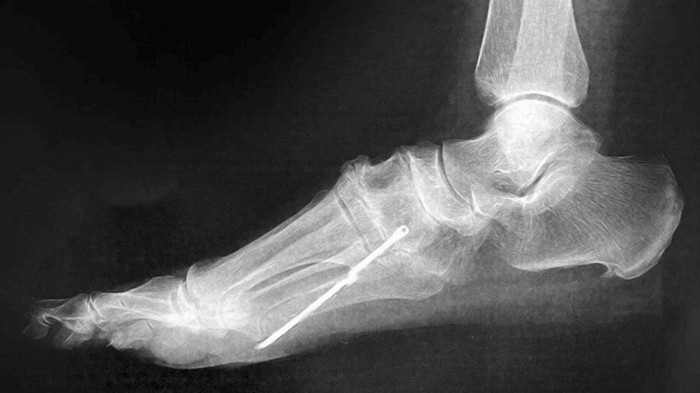

Setelah dilakukan pemeriksaan USG, dokter menemukan batang besi sepanjang 6,5 cm di dalam kakinya. Setelah ditelusuri lebih lanjut, pasien rupanya memiliki riwayat mengalami luka tembus akibat besi batang payung sekitar 40 tahun sebelumnya. (Foto: Cureus Journal)

Benda asing itu akhirnya dikeluarkan melalui prosedur sayatan kecil di telapak kaki. Benda asing tidak bisa dikeluarkan sepenuhnya, karena besi patah di dalam kaki pasien. Dokter menilai sisa besi yang tertinggal sangat berisiko jika dikeluarkan. (Foto: Cureus Journal)